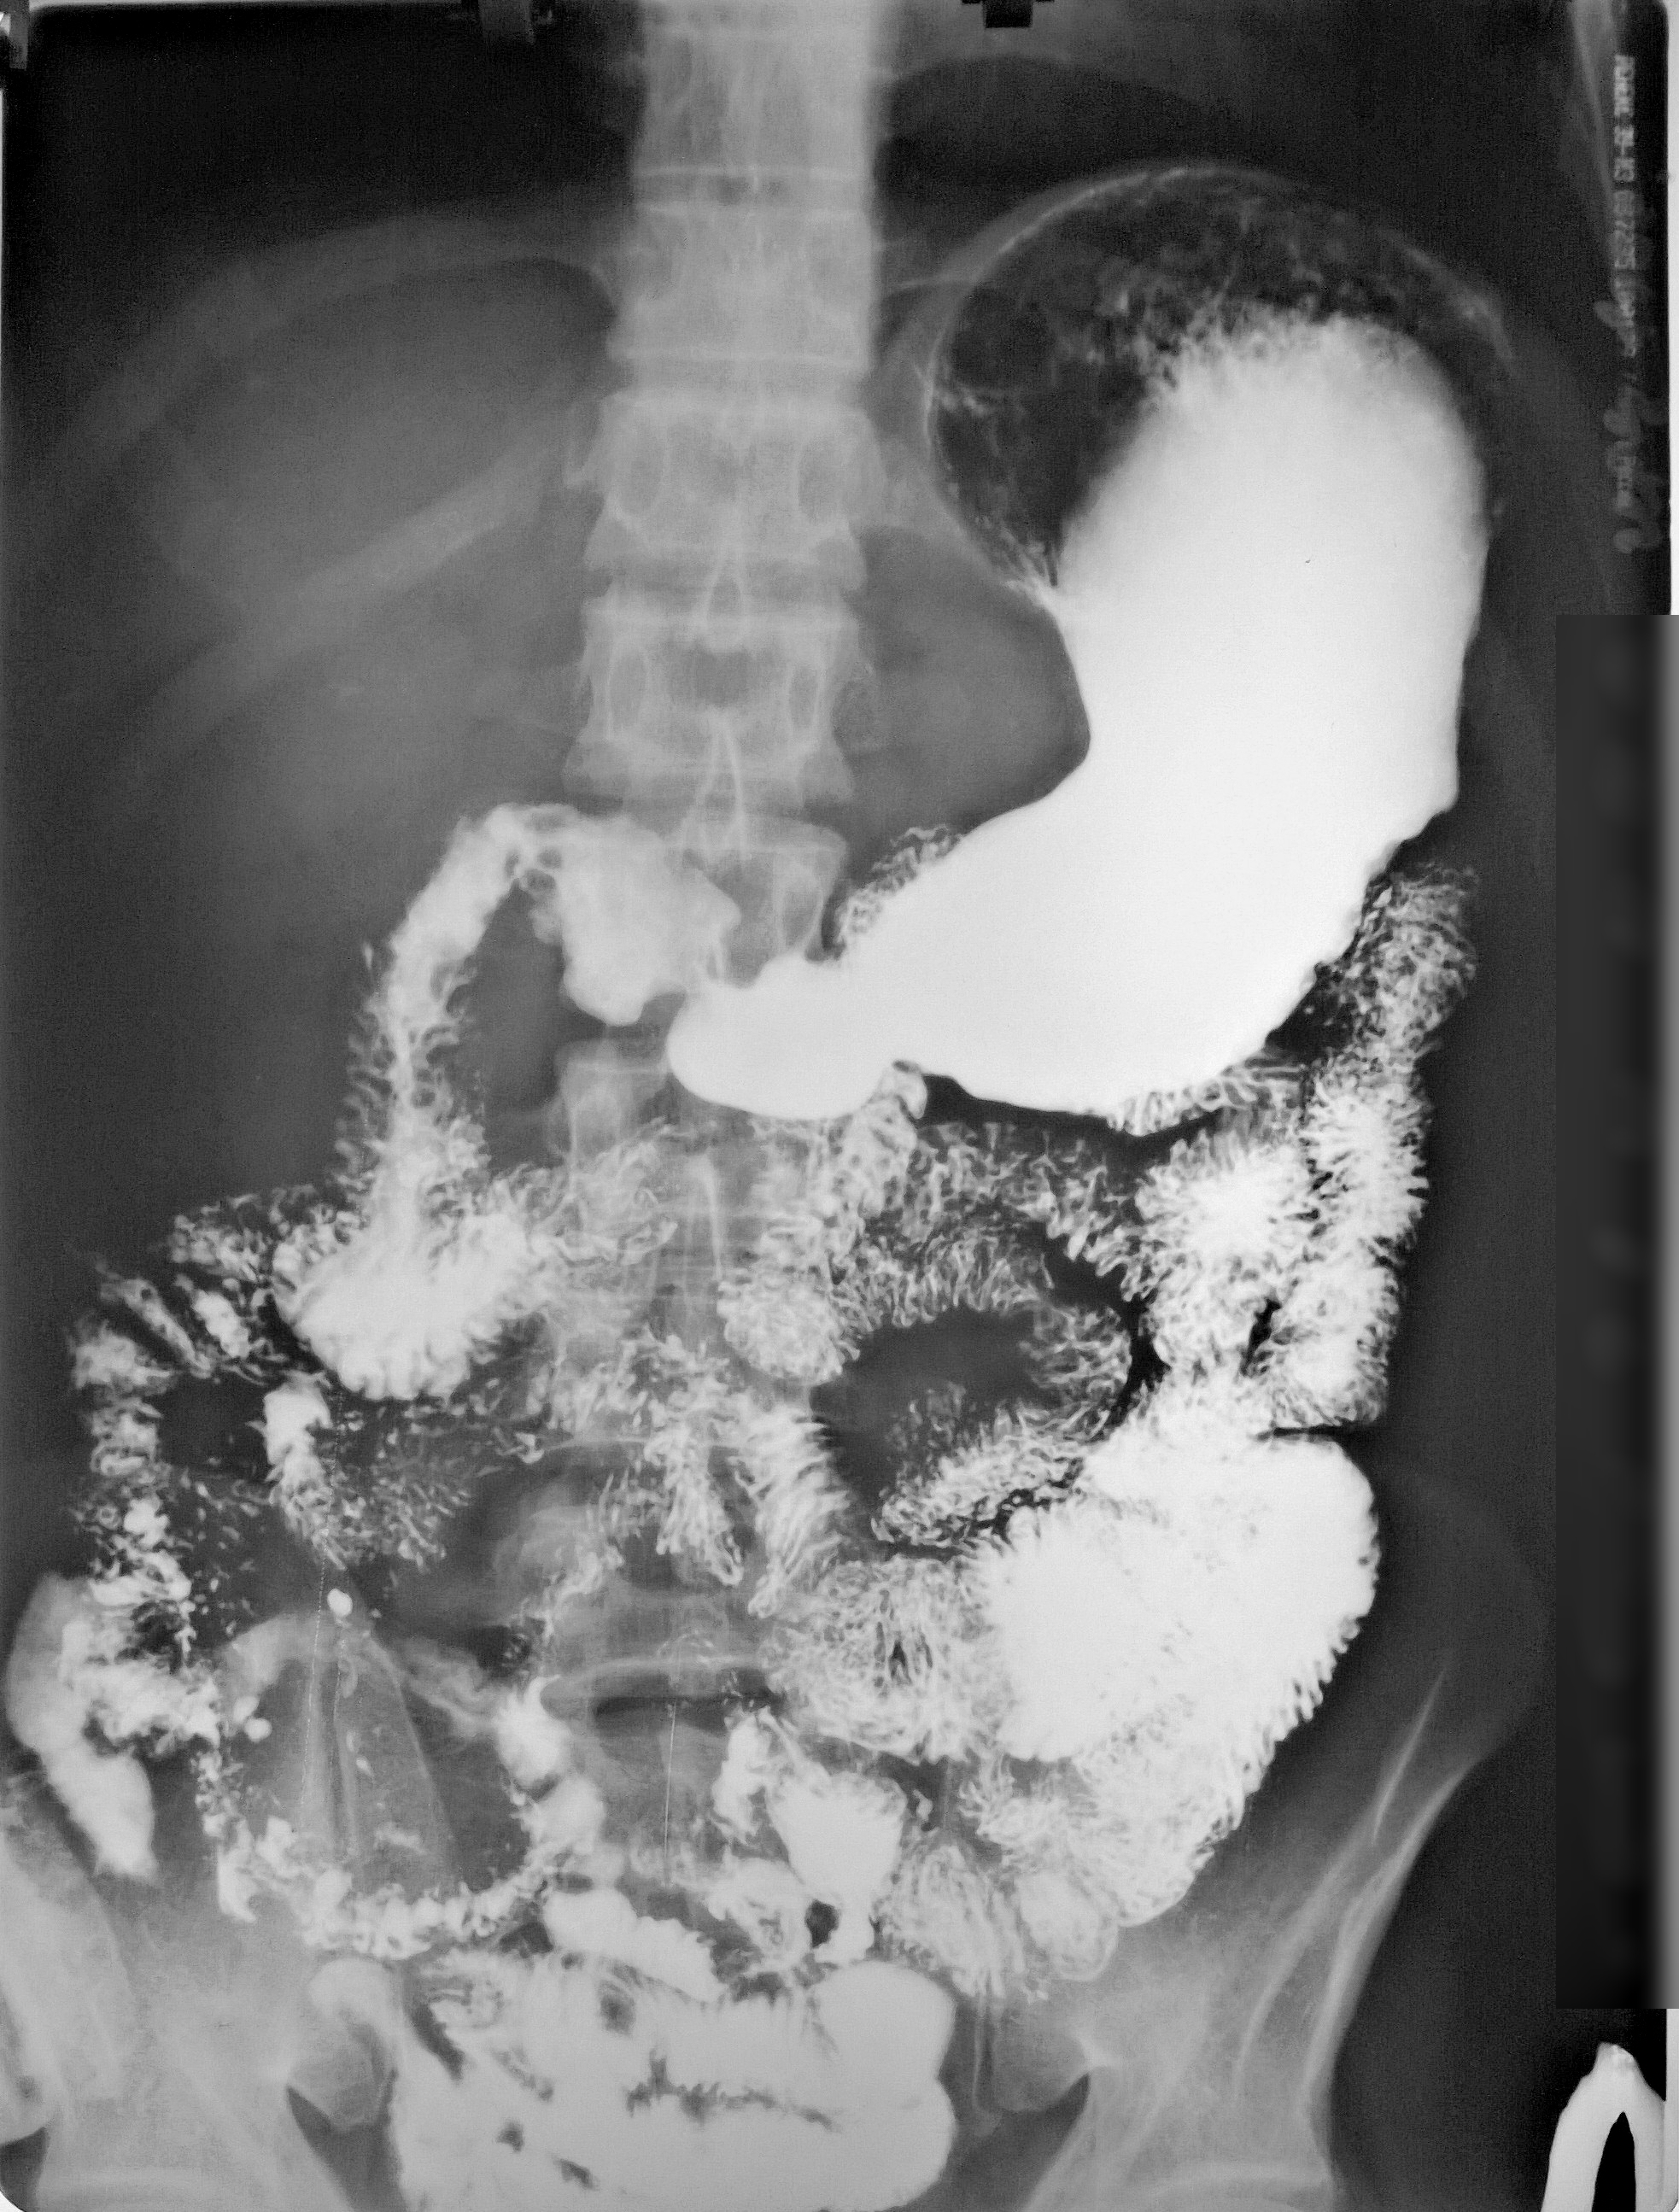

Рентгеноконтрастные Исследования Кишечника: Визуализация и Методики